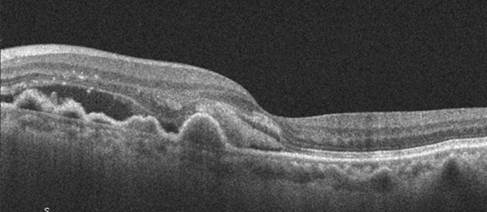

DMAE avanzada neovascular

| DMAE avanzada húmeda | NVC activa: exudación, hemorragias, desprendimiento de EPR o neurosensorial. Progresión rápida sin tratamiento | N/A | Variable | URGENTE |

OCT Macular

- Evaluación estructural de drusas, EPR, capas retinianas externas

- Detección de fluido intra/subretiniano (signo de actividad neovascular)

- Monitorización cuantitativa de la progresión (mapas de grosor, volúmenes)

- Comparación con exámenes previos (herramienta de seguimiento esencial)